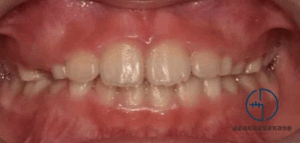

중랑구 교정치과 성장기 교정의 중요성: 비발치 교정을 통한 총생 개선

안녕하세요, 중랑구 교정치과 김정은 원장입니다. 아이들의 치아는 성장과 함께 계속 변화하기 때문에 어린 시기에 나타나는치열 문제를 어떻게 관리하느냐에 따라 향후 구강 건강의 방향이 달라질 수 있습니다. 특히나 성장기에는 턱뼈가 아직…